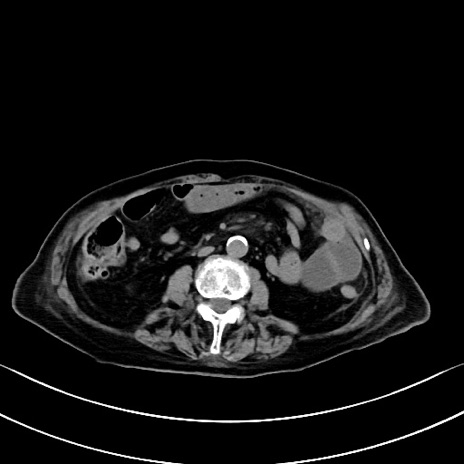

横断像

他院CT